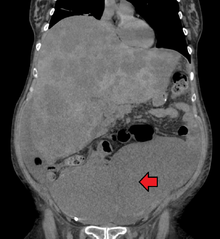

Colon cancer with extensive metastases to the liver

Colorectal cancer diagnosis is performed by sampling of areas of the colon suspicious for possible tumor development, typically during colonoscopy or sigmoidoscopy, depending on the location of the lesion. Disease extent is usually determined by a CT scan of the chest, abdomen and pelvis. Other potential imaging tests such as PET and MRI may be used in certain cases. Colon cancer staging is done next, based on the TNM system which considers how much the initial tumor has spread, if and where lymph nodes are involved and the extent of metastatis.[15]